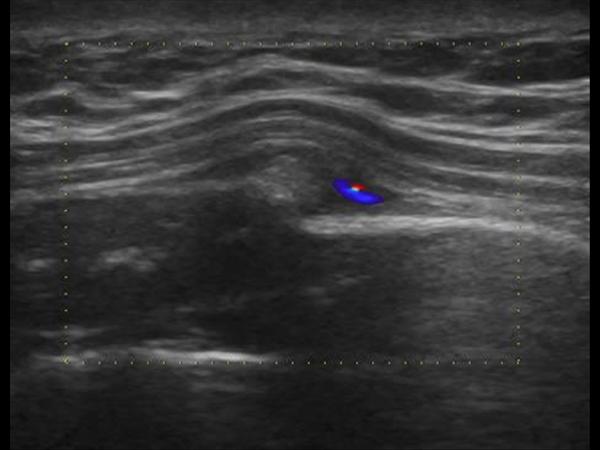

Gãy xương sườn

Gãy xương sườn - Ảnh 3

» Thông tin: Nữ giới – 52 tuổi.

» Lâm sàng: Chấn thương ngực.